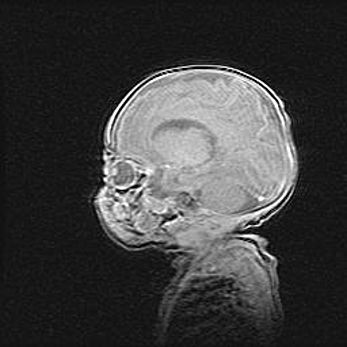

Наружная гидроцефалия с возможной атрофией височных областей.

Возраст: 28 дней

Вес: 3670 г

Пол: мужской

Окружность головы: 38 см

Срок гестации: 40 недель

Гидроцефалия головного мозга у новорожденных – это заболевание, которое характеризуется скоплением избыточного количества спинномозговой жидкости в желудочковой системе головного мозга в результате затруднения её перемещения от места выработки к месту поглощения в кровеносную систему или вследствие нарушения абсорбции. При открытой наружной форме гидроцефалии у новорожденных расширяются и переполняются субарахноидные пространства.

При нормотензивных  формах,  которые,  как  правило,  являются  следствием  перенесенных ишемических  повреждений  паренхимы  мозга,  возможно  сочетание микроцефалии  с нормотензивной гидроцефалией. В основе данных изменений лежит атрофия больших полушарий с преимущественной  локализацией  в  лобно-височных  областях.